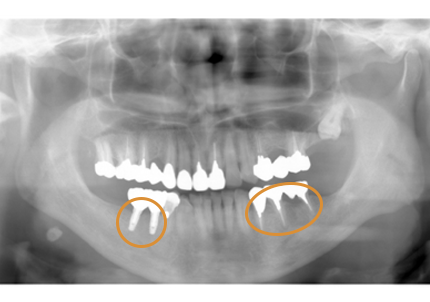

18.インプラント埋入後 パノラマレントゲン

1.初診時口腔内写真(2014年6月)

3.前回治療後5年経過(2021年2月)

【左下ブリッジ5番6番歯根破折の為要抜歯】

5.インプラント埋入(2021年6月)

右下2本初診より9年経過、左下3本埋入後4年経過、ともに経過良好。